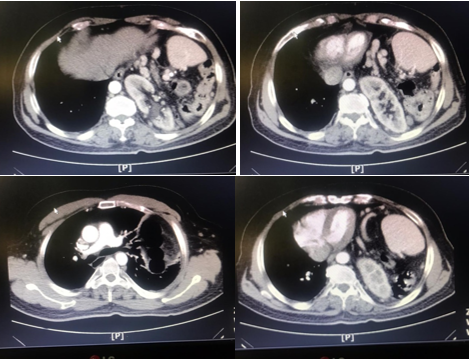

The patient has no history of major trauma or abdominal surgery, except for a history of trisomy 21 and left foot fracture, and is not taking any medication. At the emergency department, blood pressure was 125/75 mmHg, heart rate: 88 beats/min, O2 saturation: 92 %, respiratory rate: 18/min, and temperature: 37o C. The physical examination revealed abdominal tenderness in LUQ without rebound and guarding and reduced respiratory sound in the lower part of the left lung. The patient's ECG was normal. Abdominal and chest x-rays showed that the loops of the colon were located in the left hemithorax (Figure 1). In further examination, a computed tomography scan of the thorax and abdomen with oral and intravenous contrast revealed a large diaphragmatic hernia with a displacement of the left kidney, spleen, and parts of the small intestine and colon into the thoracic cavity (Figure 2). The patient had normal lab tests except WBC 10500 with PMN 85%. In echocardiography, LVEF was reported 45%, without ASD and VSD with moderate MR.

Figure 2 CT scan of the thorax and abdomen with oral and intravenous contrast.